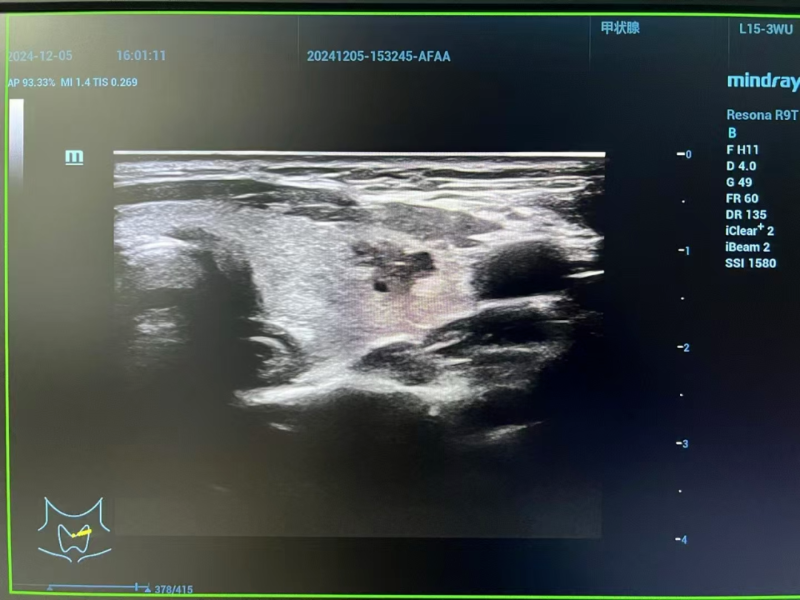

△術中情況

手術開始,嚴格遵循無菌規范,周密完成消毒鋪巾流程后,局部麻醉精準施行,確保患者全程清醒且舒適。于高清超聲實時導航下,手術團隊憑借精湛技藝,巧妙操控微波消融針,如靈動舞者穿梭于復雜解剖迷宮,精準穿刺靶向結節,高效釋放能量,使癌灶消融于無形。期間,憑借超聲的敏銳“慧眼”,成功規避重要血管、纖細神經及毗鄰關鍵器官,將手術風險降至最低,全程如精密鐘表運行,精準無誤、平穩有序。